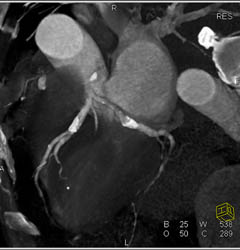

Calcified Plaque LAD W/o Stenosis in Multiple Views